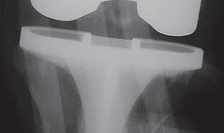

Posterior Cruciate Ligament-Retaining TKA: Navigating Pitfalls

P ITFALLS Correct rotational positioning of the femoral and tibial components is a prerequisite for a success…